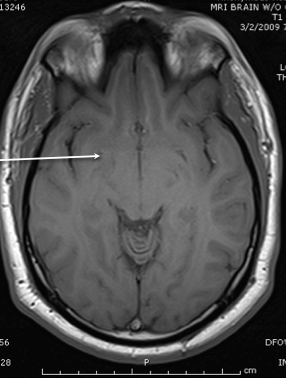

posterior horn of the internal capsule

thalamus

anterior limb of the itnernal cpasule

lateral ventricle